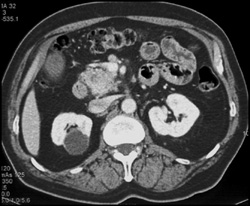

Intraductal Papillary Mucinous Neoplasm (IPMN) Infiltrates the Entire Gland